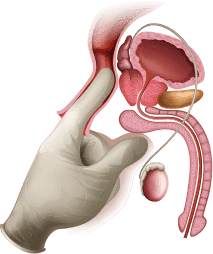

ponižavajućim medicinskim procedurama

28,573 muškarca

od strane stručnjaka

testiran

Prema službenim podacima od strane SZO, svaki drugi

muškarac preko 30 godina starosti ima kronični

prostatitis.

85% muškaraca preko 20 godina pati od kroničnog

prostatitisa.